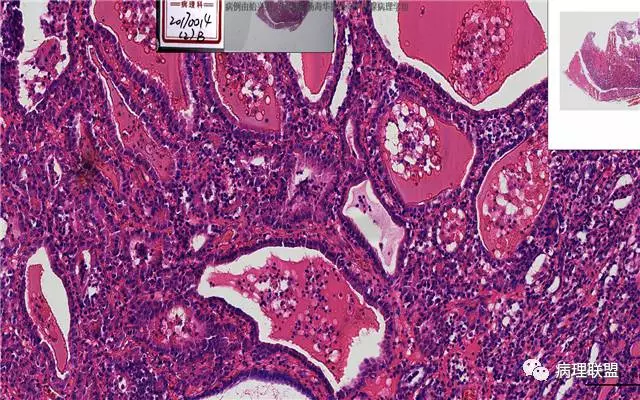

患者,女,45岁,发现双侧甲状腺肿物半月余。大体所见:左侧甲状腺肿物:4.3*5*4cm肿物一个,包膜完整,光滑,质脆,中央见出血。右侧甲状腺组织:3*1.6*1.5cm及1*1*0.8cm组织两块,其中较大的组织切开见内有0.8cm及1.2cm两个,质硬,灰白色,界不清,较小的,切开见灰黄色,质脆。